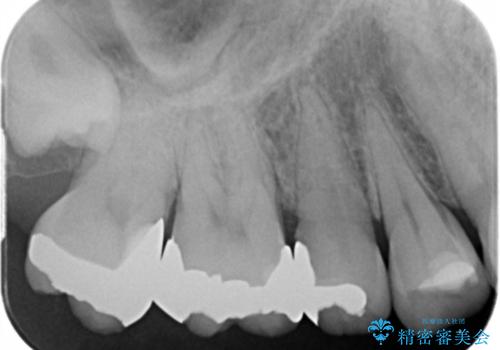

- 冷たいものがしみて飲み物が飲めないとの事で来院。

歯肉が退縮していたので歯周外科手術(歯茎の移植手術)か被せ物で覆う(歯肉退縮しているところまで覆う)の提案をしたところ被せ物がいいとのことでしたので

適合の良い被せ物が入りました。

一つ前の歯も後に染みてくる可能性があるとの事で被せ物をするか検討中です。